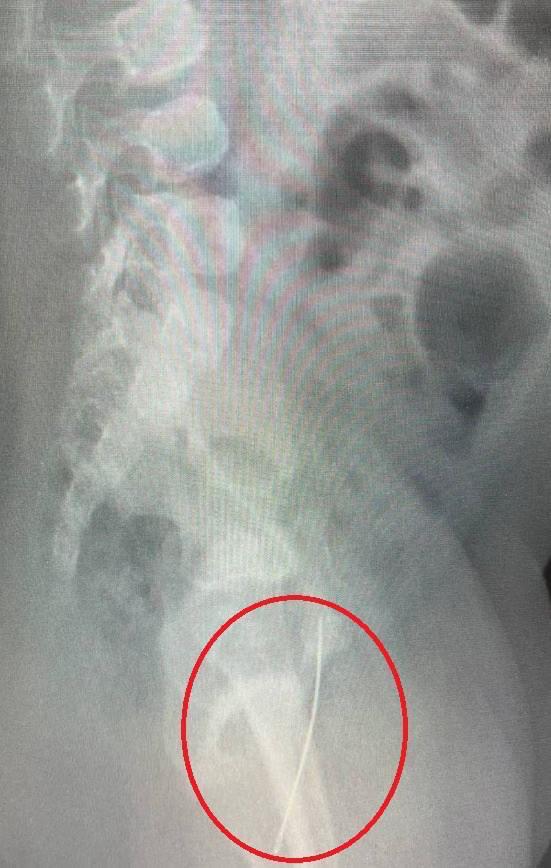

Врачи достали швейную иголку из годовалого ребёнка

Врачи достали швейную иголку из годовалого ребёнка. Предположительно, малыш на неё сел.

У него была сильная боль в промежности, он даже не мог встать на ноги. Операция прошла успешно, обошлось без осложнений, сообщили в Минздраве Московской области.